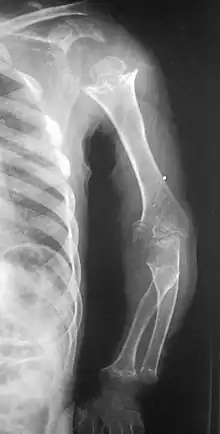

| Pseudoachondroplasia. Shoulders and Humeri. Note the dysplastic proximal humeral epiphyses, metaphyseal broadening, irregularity and metaphyseal line of ossification. These changes are collectively known as "rachitic-like changes". Lesions are bilateral and symmetrical. | |

- Dysplastic/hypoplastic epiphyses especially of shoulders and around the knees.

- Metaphyseal broadening, irregularity and metaphyseal line of ossification. These abnormalities that are typically encountered in proximal humerus and around the knees are collectively known as “rachitic-like changes”.

- Radiographic lesions of the appendicular skeleton are typically bilateral and symmetric.